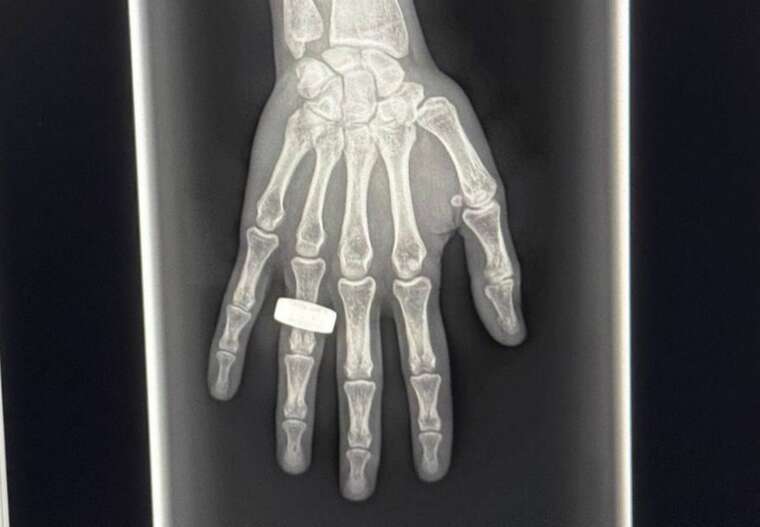

Екіпаж Fram2 вперше зробив рентгенівський знімок у космосі

Про це повідомив керівник місії Чун Ван у мережі Х.